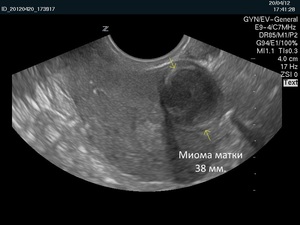

Основная цель диагностики опухоли заключается в определении размеров миомы. Этот параметр играет ключевую роль в выборе метода лечения. Обычно размеры измеряются в миллиметрах или сантиметрах, и сопоставляются с увеличением матки в зависимости от срока беременности.

- Более точные данные можно получить после проведения УЗИ, КТА или МРТ органов малого таза;

- Сонографическое исследование позволяет визуально оценить увеличение размеров матки;